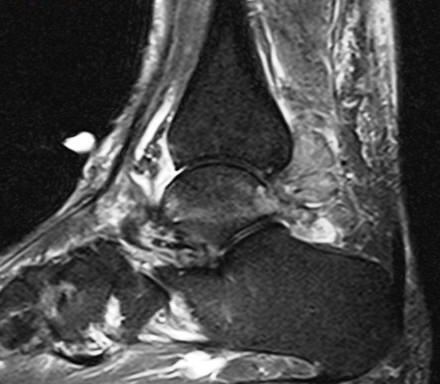

Figure 2 for case Gout arthritis ( RID3567 )

Figure 2